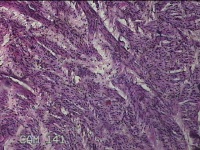

直肠粘膜

性别

女

年龄

31岁

临床诊断

混合痔

一般病史

反复肛门肿块、出血2年。

标本名称

大体所见

灰白暗红色条索状组织4.5x1.3x0.8cm一块,表面糜烂,切面灰白暗红色,质软。

似痔。